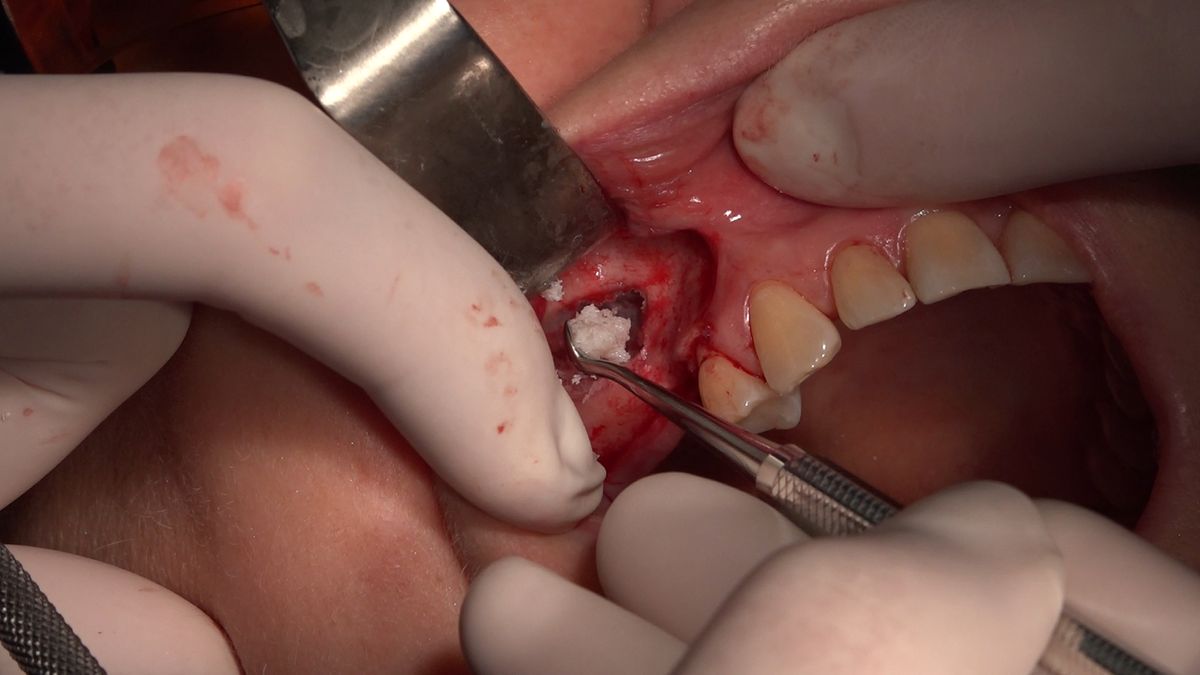

Practiculum Implantologii – Sezon VIIB, sesja 7, dzień 2